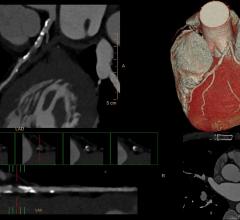

Results from the PROMISE clinical trial confirmed what many cardiologists and radiologists have long suspected to be true: Coronary computed tomographic angiography (coronary CTA) is extraordinarily effective in accurately diagnosing patients with low to moderate chest pain.